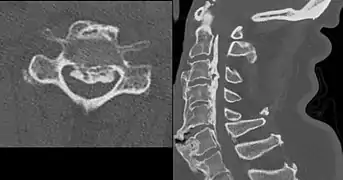

Confluent ossification of multiple contiguous vertebral bodies in diffuse idiopathic skeletal hyperostosis (DISH)

Ossification of the posterior longitudinal ligament in DISH